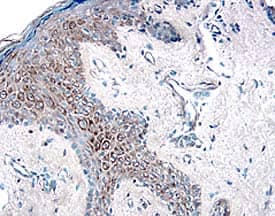

HGF Receptor/c-MET in Human Skin.

Hepatocyte Growth Factor Receptor (HGF R)/c-MET) was detected in immersion fixed paraffin-embedded sections of human skin using Human HGF R Antigen Affinity-purified Polyclonal Antibody (Catalog # AF276) at 15 µg/mL overnight at 4 °C. Tissue was stained using the Anti-Goat HRP-DAB Cell & Tissue Staining Kit (brown; Catalog # CTS008) and counterstained with hematoxylin (blue). View our protocol for Chromogenic IHC Staining of Paraffin-embedded Tissue Sections.

This antibody specifically recognizes human HGF R. In ELISA and Western blot experiments, this antibody shows approximately 30% cross-reactivity with recombinant mouse HGF R.